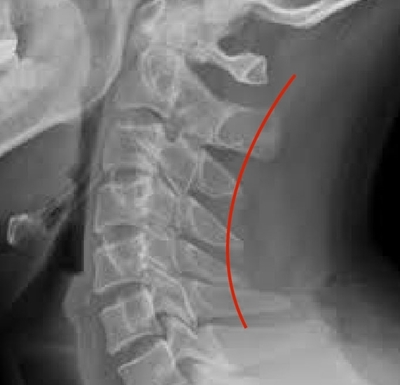

척추는 아래와 같이 경추, 흉추, 요추로 크게 나눌 수 있는데 흉추는 후만이고 나머지는 전만입니다.

무슨 말이냐 하면 흉추는 뒤로 커브를 그리고 있고 나머지는 앞으로 커브를 그리고 있는게 정상이라는 말이죠.

아래 사진처럼 S 자를 그리게 말이죠.

X-Ray를 보면 요추의 전만을 확인할 수 있습니다.

저렇게 전만이 되지 못하고 점점 후만이 되어가면서 디스크에 통증이 오는건데요.